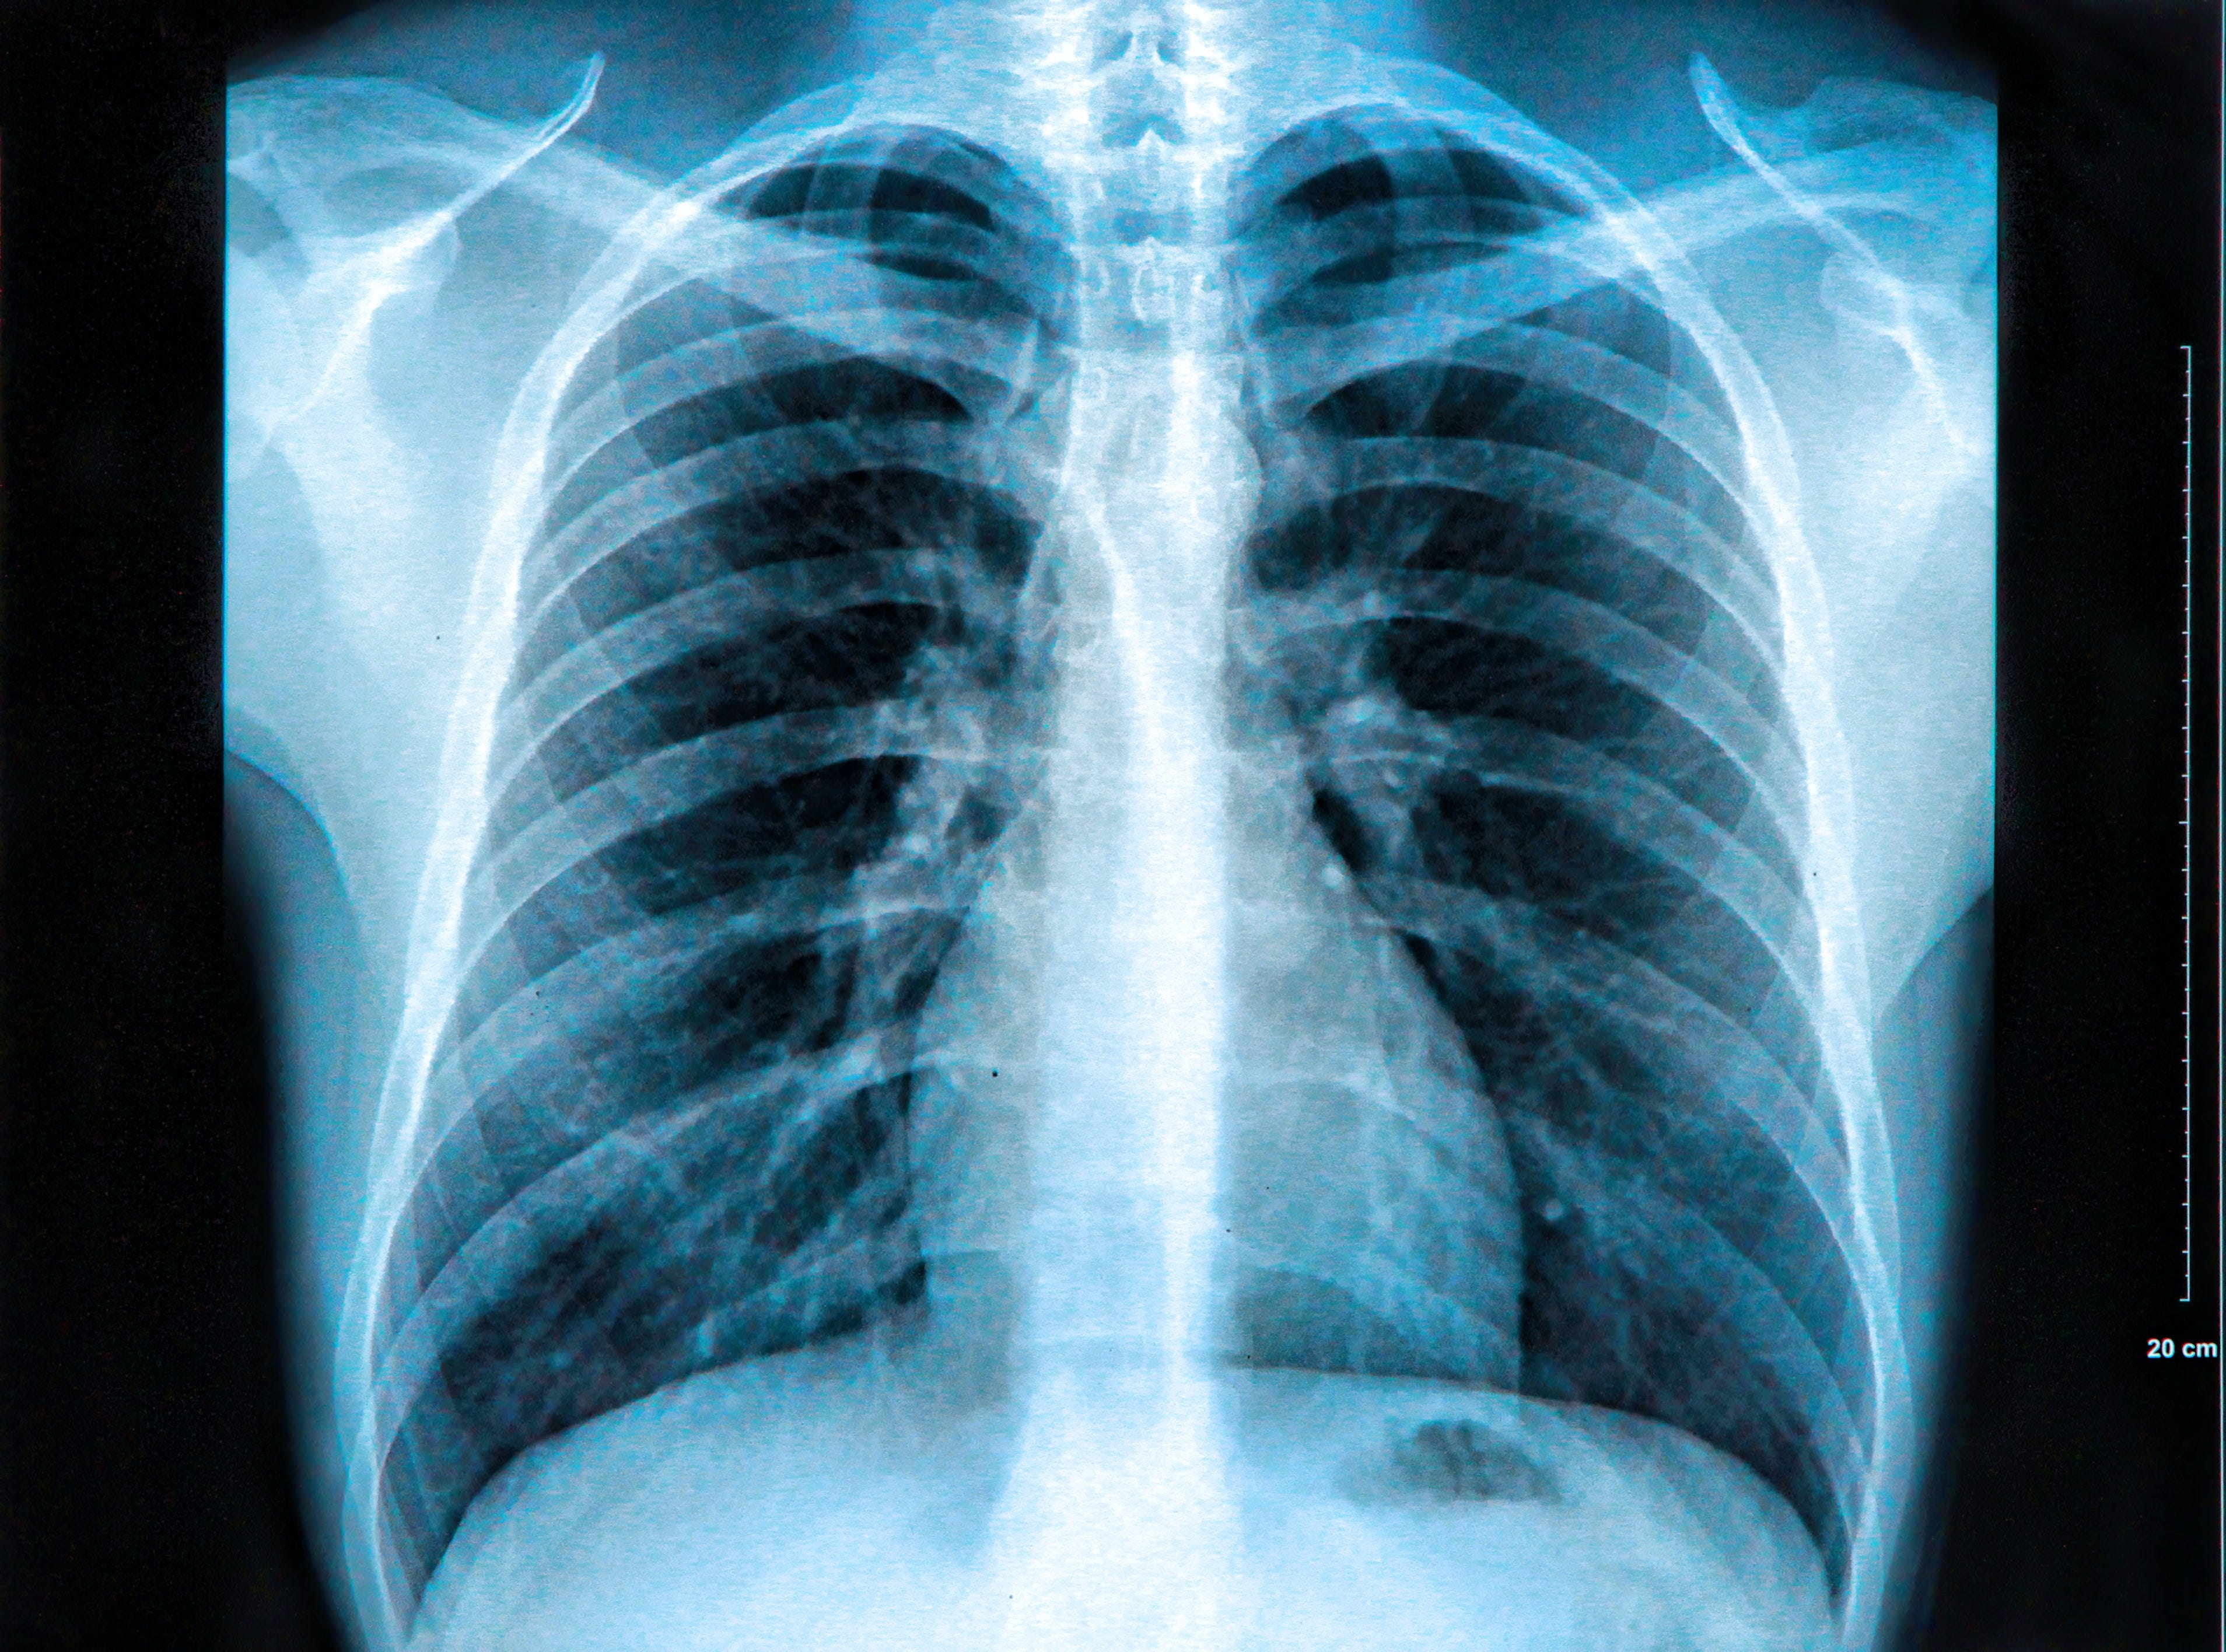

Можно ли делать рентген грудной клетки при месячных - фото презентация